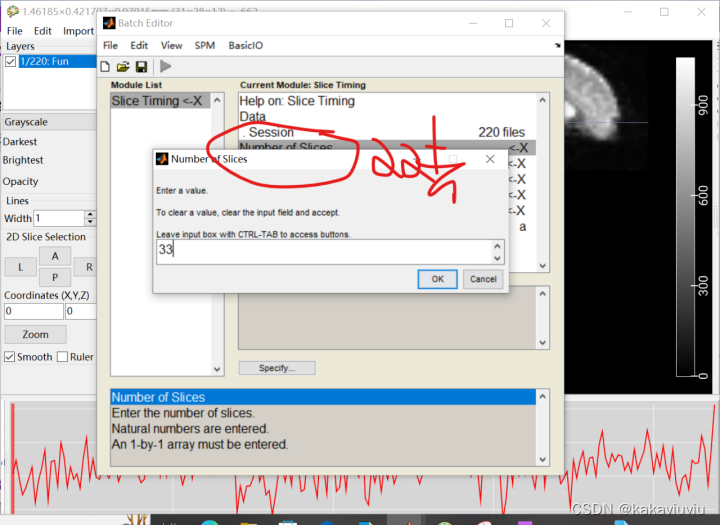

打开spm,点击slice timing--data--点击session

扫描层数:33层

填写TA